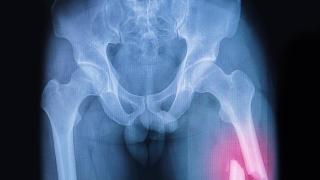

Durante el tiempo que desarrollan esta actividad, se ven comprometidas las zonas cervical y lumbar. La que más sufre es la vértebra C7, al final del cuello, porque es sobre la que recae todo el peso que levantan.

En la zona cervical las lesiones más comunes son las contracturas y las inflamaciones por los traumatismos que pueden sufrir al portar el paso. "La columna puede envejecer antes y generar, incluso, hernias de disco", agrega el experto, que también ha sido costalero. Este problema puede aparecer si la práctica se lleva a cabo un año tras otro y no se hace de manera adecuada, debido al desgaste de los discos intervertebrales.

Este tipo de hernia puede aparecer, incluso, después de que una persona haya dejado de ser costalera. El desgaste que provoca esta actividad en los discos intervertebrales genera una sobrecarga que años después puede desembocar en este tipo de lesión e, incluso, en daños en los nervios, dice el cirujano.

El especialista recuerda que para alzar el trono también tienen que ir muy acompasados y hacer ese movimiento al unísono. Si no es así, los que se adelanten pueden hacerse daño por cargar con más peso del correspondiente. Por otro lado, los que se retrasen pueden provocar que sus compañeros levanten más de lo que les toca, con las sucesivas consecuencias. Este tipo de fallos puede desembocar en que alguno de ellos sufra una fractura cervical o hematomas en esa zona, informan desde la GEER.

Si el trono se levanta lentamente, lo mejor es aumentar la lordosis lumbar, señala el especialista. Es decir, arquear la espalda dejando los glúteos hacia afuera. De esta manera, se protege esta zona baja, ya que si se realiza el movimiento con la espalda flexionada hay más posibilidad de que aparezca una hernia.